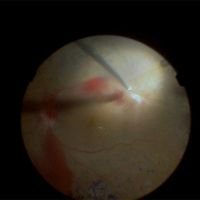

Retinal Detachment Surgery: Tips and Tricks Part 1

Mariano Iros, Tomás Castro Feijóo, Ahmed Sallam, Abdallah Ellabban, Frank Becquet, Juan Francois Le Rouic -

Retinal Detachment Surgery: Tips and Tricks Part 2